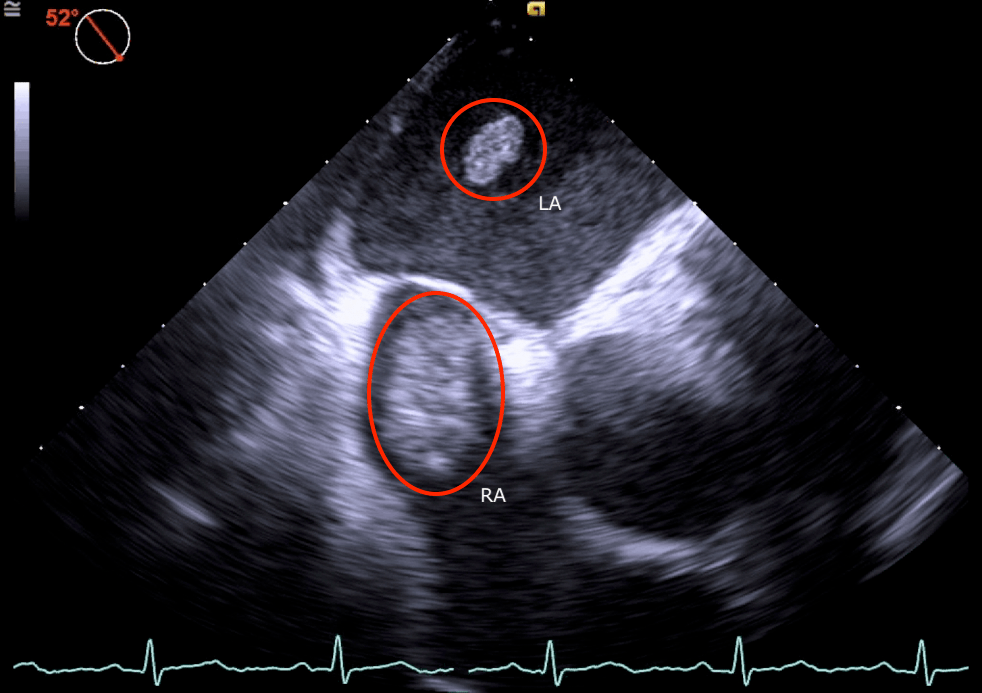

Right atrial thrombus. Transesophageal longaxis view. RA = right Ra Thrombus Medical Abbreviation Pulmonary embolism (pe) due to right atrial (ra) thrombus is gaining increasing recognition as a common clinical problem. The best management modality has not yet been. Floating right heart thrombi (rht) probably represent an extreme medical emergency in the context of acute pulmonary embolism (ape) [1]. Thrombosis* right atrial thrombi is a serious complication of central venous cannulation although incidence. Ra Thrombus Medical Abbreviation.

Transthoracic echocardiogram (TTE) showing thrombus in the right Ra Thrombus Medical Abbreviation The prevalence of rht in the setting of pe is. Floating right heart thrombi (rht) probably represent an extreme medical emergency in the context of acute pulmonary embolism (ape) [1]. The best management modality has not yet been. The best management modality has not yet been established. Pulmonary embolism (pe) due to right atrial (ra) thrombus is gaining increasing recognition. Ra Thrombus Medical Abbreviation.

Echocardiogram showing RA thrombus from IVC into RA across Tricuspid Valve. Ra Thrombus Medical Abbreviation The best management modality has not yet been established. Thrombosis* right atrial thrombi is a serious complication of central venous cannulation although incidence is less as compared to left atrial. Pulmonary embolism (pe) due to right atrial (ra) thrombus is gaining increasing recognition as a common clinical problem. The best management modality has not yet been. Floating right heart thrombi. Ra Thrombus Medical Abbreviation.